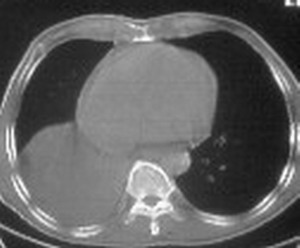

标题: CT6943:[讨论]胸部,M/67Y,体检发现。

ct值约12hu。

ct值约12hu

右肺下叶支气管阻塞,右下叶不张,考虑中心型肺癌伴下叶不张

先考虑:右下肺中心型肺癌伴下叶肺不张、胸腔积液

右肺下叶支气管闭塞,中间段支气管狭窄,下叶不张,胸腔及叶间积液.中心型肺癌伴下叶肺不张.胸腔和叶间积液.

考虑中心型肺癌伴下叶不张,肺底积液吧。

右肺下野后部均匀低密度影,边缘锐利,前缘外突(不支持肺不张),纵隔内未见明显肿大淋巴结,右下肺门结构显示欠清,临床资料太过简单,考虑右侧后胸部包裹性积液。其他待排。建议密切结合临床其他检查。

考虑右下肺中心型肺癌伴下叶肺不张、胸腔积液。